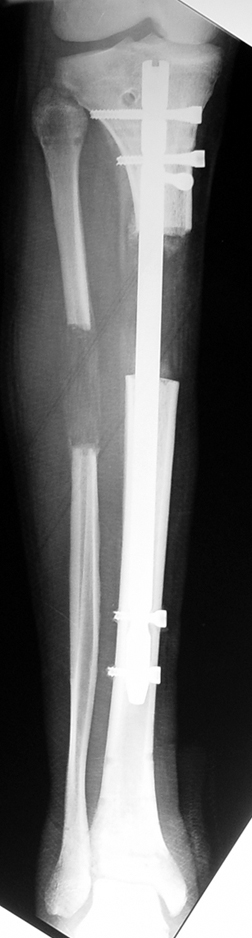

In selected cases, we prefer to use a combination of a unilateral dynamic axial fixator and an interlocked intramedullary nail, in order to protect the length and alignment after the completion of the lengthening procedure. As a prerequisite for this technique, the narowest diameter of the medullary cavity shall be wider than 7 mm and the length of the nail segment distal to the osteotomy site shall be at least 8 cm. after the completion of the lengthening procedure.The intramedullary nail neutralizes shear and bending forces on femur during lengthening, shortens external fixation time, and protects newly formed bone against fractures. In our series, subtrochanteric osteotomy was performed in one case. No varus angulation occured despite the intramedullary nail.

Ilizarov stressed the significance of endosteal blood circulation for distraction osteogenesis. Although we placed the intramedullary nail after reaming the femur in all cases, the time for callus formation was not longer than expected. Thus we found that there is no slowing in the rate of new bone formation due to disruption of medullary blood flow. The rationale of this finding is revascularization that occurs following reaming of the medullary cavity, the fixation stability with the intramedullary nail and early functional weight bearing. The potential disadvantages of a combined use of external and internal fixation metods are increased blood loss, intramedullary infection, risk of fat embolism and excessive metal load.The most fearsome complication is a deep intramedullary infection (panosteomyelitis) triggered by pin tract infection.No such complication was encountered in our series. In order to avoid this complication, after the completion of lengthening the nail shaill be interlocked from the medial side, and contact of internal and external fixator pins shall be avoided.

Despite low sample size, our aim was to compare two groups with matching ethiology, age, location and amount of the deformity and other similar factors. We neglected simultaneous tibial lengthening and osteotomy site in this preliminary study. The sample size was not enough to conduct a prospective randomized trial. Although the results of the study did not produce statistically significant data, it is the first and only example in our country and conveys significant experience.

The combination of intramedullary anil and dynamic axial external fixator is harder as a technique than Standard Ilizarov applications. However, it is stil appealing due to the following advantages: shortening of the duration of external fixation, protection against refracture, early rehabilitation, gaining maximum range of motion and daily quality of life. These advantages are more important than disadvantages such as increased cost, increased blood loss and potetntial deep infection. All in all, we believe that the technique of femoral lengthening over an intramedullary nail is a safe and reliable method and provides advantages over standard Ilizarov aplications.